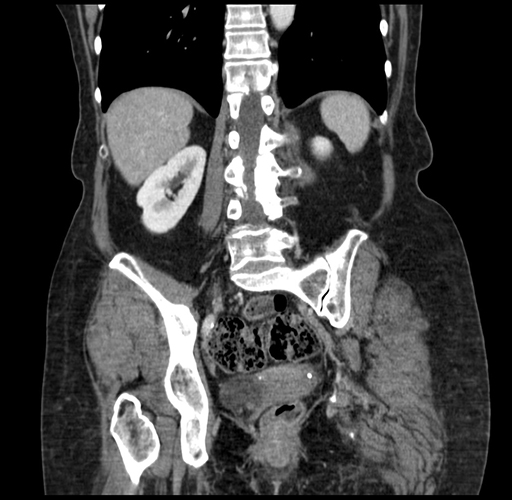

Pre-Chemo: Coronal Venous